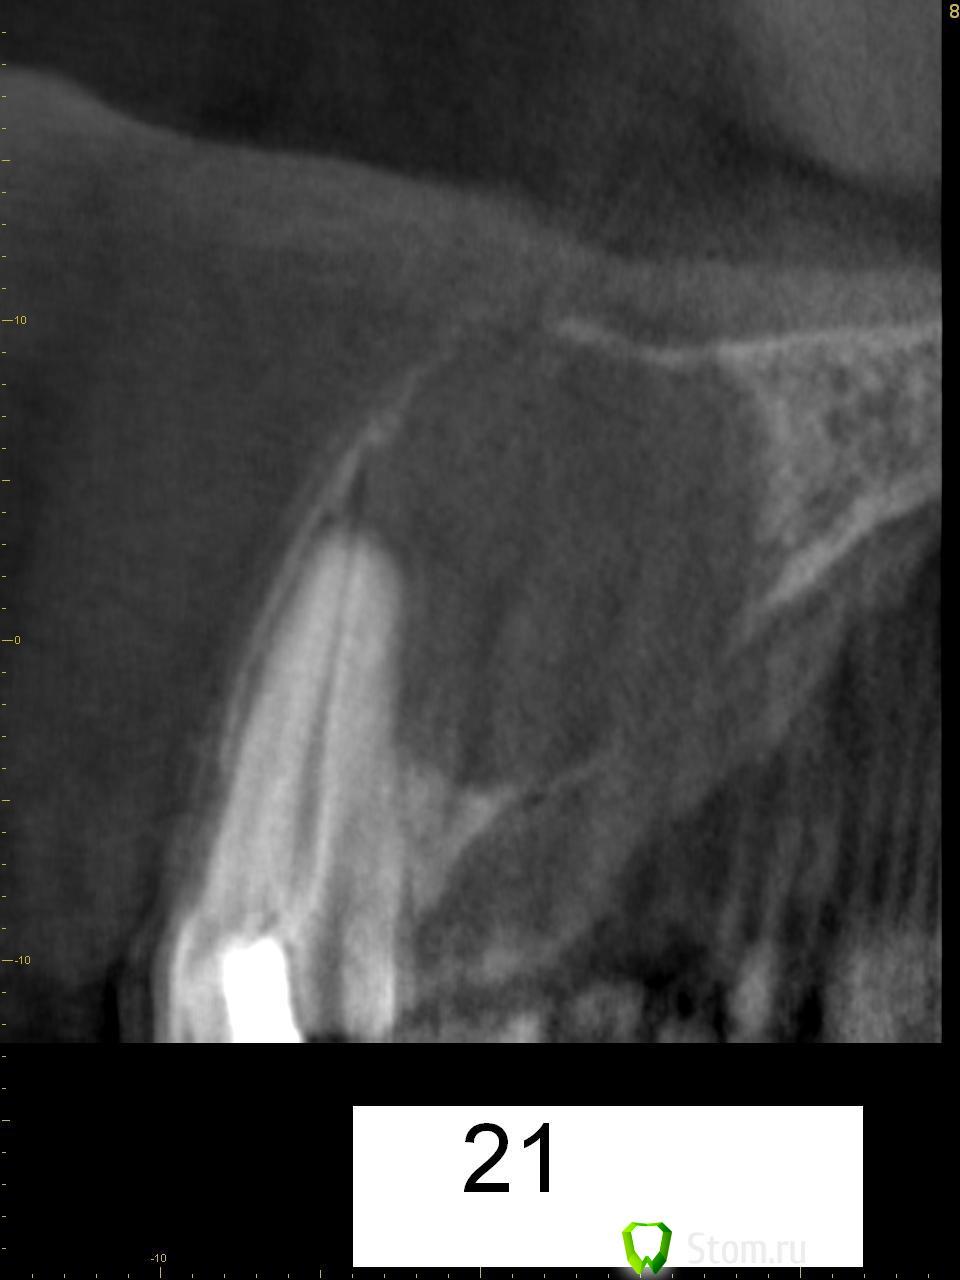

kriokov Опубликовано 20 марта, 2012 Поделиться Опубликовано 20 марта, 2012 Пац 60 лет, 13.03- диагносцирована нагноившаяся киста в\челюсти, вскрыт гнойник, антибактериальная и симптоматическая терапия. На КТ киста до 4 куб см ориентировочно, сквозной дефект с вестибулярной на небную поверхность, деструкция носонебного канала, деструктивный очаг небно за корнем 11. дно носа не критично. Имплантация в перспективе не планируется.Через 1 месяц планируется штатная цистэктомия с удалением 21 и 22. Коллеги, кто как небно мебрану выставляет? Дефект кости на небе 10 на 10 мм. Сам думаю, что под полнослойный лоскут на небе придется устанавливать, попробую отслоиться со стороны костной раны. Ссылка на комментарий

K_gur Опубликовано 3 июня, 2012 Поделиться Опубликовано 3 июня, 2012 Господа ! Пациенту 2009 - ом было 62 года, киста на 11-ом , решили одномоментное удаление, цистэктомия, аугментация и имплантация, Вот снимки! подледный снимок новый. Будут ли замечания? Но самое интересное что пациент да сей пор не добрался до ортопеда, сделает коронку выложу и этот снимок.http://s019.radikal.ru/i625/1206/30/434cde3231d2.jpghttp://s019.radikal.ru/i630/1206/cc/20a47ecf2a78.jpg http://s06.radikal.ru/i179/1206/49/7f6119696343.jpghttp://s019.radikal.ru/i604/1206/d6/77c4408b76ff.jpg http://i064.radikal.ru/1206/74/5f59a960ba3d.jpghttp://s017.radikal.ru/i440/1206/ad/40fae14fa38a.jpg Ссылка на комментарий